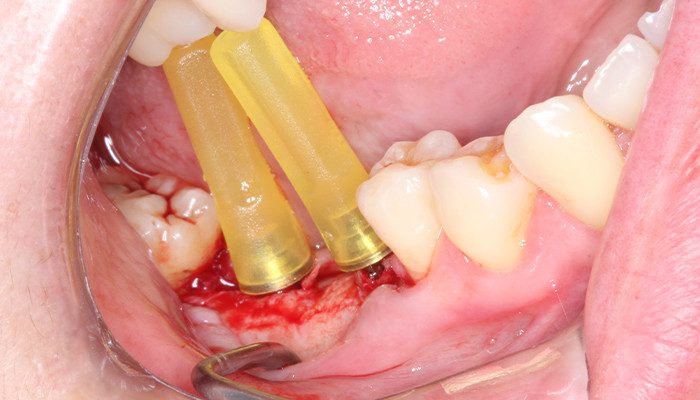

12 | Mini pilares Aikkon sendo instalados.

13 | Mini pilares Aikkon instalados após torque final.